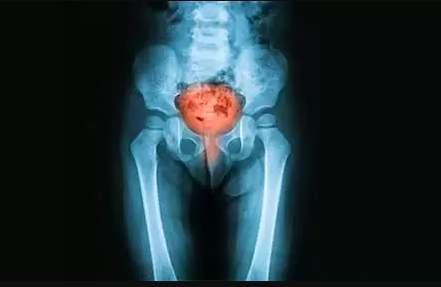

İdrar yolu tıkanıklığı: Böbrek taşları idrarı mesanede tutabilir ve bir İYE’ye yol açabilir. Bir tıkanıklığınız varsa, mümkün olan en kısa sürede tedavi edilmesi önemlidir.

Bağışıklık sistemi zayıf olan veya böbrek taşı veya prostat büyümesi gibi mesanenin tamamen boşaltılmasını zorlaştıran bir durumu olan kişilerde İYE olma olasılığı daha yüksektir. Diyabet, orak hücreli anemi, pıhtılaşma bozukluğu olanlar ve tıbbi tedavi için kateter kullanan kişiler de enfeksiyon riski altındadır.

Doktorunuzun enfeksiyon tipini teşhis etmesine ve en iyi tedaviyi belirlemesine yardımcı olmak için idrar kültürü, kan testi, CT taraması veya MRI yapılabilir. Enfeksiyon şiddetliyse, antibiyotik almanız gerekebilir.